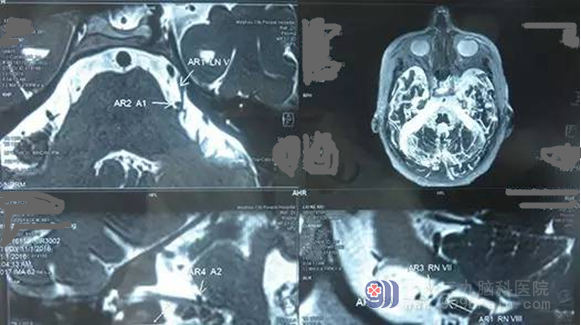

神经外一科接诊了一位86岁的高龄患者,8年前开始出现左侧面部疼痛,在当2家医院医治,但无明显改善。老人描述自从得了这个病,洗脸、刷牙甚至说话、吃饭都不敢太用力,太难受了!为求进一步治疗,来我院就诊。入院后完善检查,诊断:三叉神经痛。神经外一科主任张良主刀为老人行左侧三叉神经痛微血管减压术, 术程顺利,经系统治疗后患者恢复良好,未有颜面部疼痛症状。

广东三九脑科医院神经外一科张良主任介绍,三叉神经痛微血管减压术的原理是找到三叉神经和责任血管,用Teflon垫片将血管与神经根隔离。一旦责任血管被隔离,产生刺激的根源就消失了。